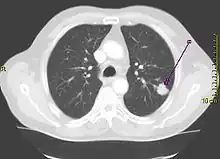

| A chest X-ray showing a tumor in the lung (marked by arrow) | |

A person suspected of having lung cancer will have imaging tests done to evaluate the presence, extent, and location of tumors. First, many primary care providers perform a chest X-ray to look for a mass inside the lung.[8] The X-ray may reveal an obvious mass, the widening of the mediastinum (suggestive of spread to lymph nodes there), atelectasis (lung collapse), consolidation (pneumonia), or pleural effusion;[9] however, some lung tumors are not visible by X-ray.[5] Next, many undergo computed tomography (CT) scanning, which can reveal the sizes and locations of tumors.[8][10]